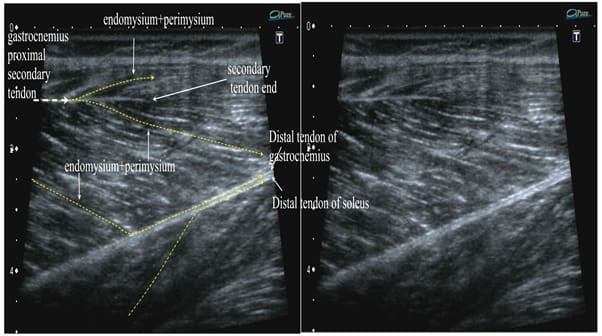

Histology-US Correlation

The whole tendinous system can be clearly visualized by ultrasound. The tendons as well as perimysium+endomysium show in a relaxed muscle as hyperechogenic lines of different thickness. Skeletal muscles show 0,1-0,4mm of anechoic space between the bright lines and that is 4 to16 myofibers (depending of the size of myofibers) per dark space between the lines of endomysium + perimysium in a relaxed state, neutral position. Figures 17,18,19 show the US images of selected muscles.